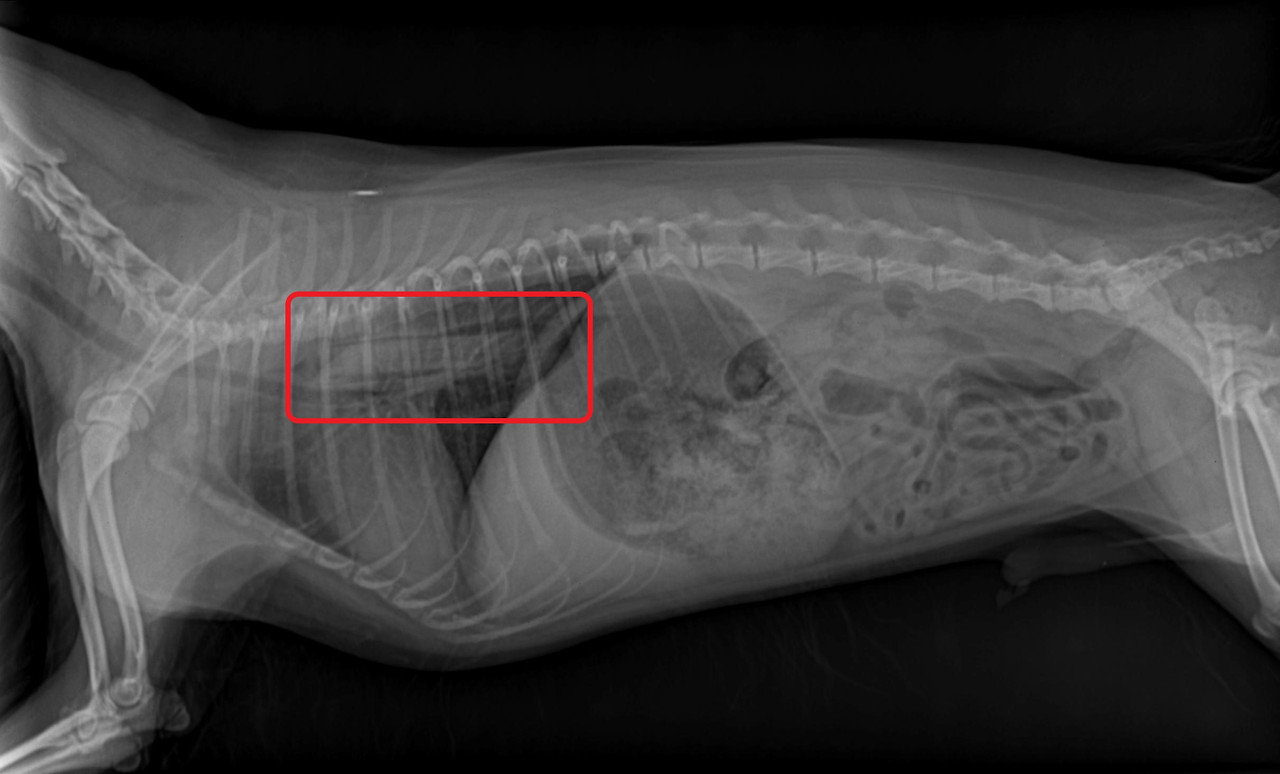

강아지가 이물을 먹어서 병원에 오는 사례

2.jpg

1.jpg

<좌> 식도에 사과가 걸린 경우 내시경 사진, <우> 식도에 개껌이 걸린 경우 방사선 사진

사진출처 : 24시 센트럴 동물 메디컬센터

아동기는 호기심이 왕성하고 에너지가 넘치는 시기라고 말씀드렸는데요,

이 때문에 먹어서는 안 되는 이물을 먹거나 급하게 먹다가 식도에 걸려서 병원에 오는 사례가 많습니다.

3.jpg

KakaoTalk_20200529_124245332.jpg

<좌> 식도에 간식이 걸린 경우 <우> 위에 옷핀과 동전이 있는 경우